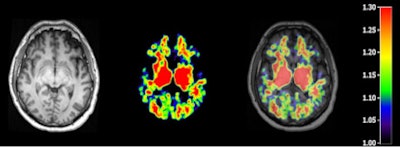

T1-weighted MR (left panel), C-11 PiB PET (middle panel), and fused image (right panel) from a patient 48 hours following severe traumatic brain injury. Image courtesy of Dr. David K. Menon, PhD.

T1-weighted MR (left panel), C-11 PiB PET (middle panel), and fused image (right panel) from a patient 48 hours following severe traumatic brain injury. Image courtesy of Dr. David K. Menon, PhD.At the same time, PET imaging techniques with several carbon-11-labeled and F-18-labeled ligands to view beta amyloid in the brain have been developed and used in Alzheimer's research. Pittsburgh Compound B, for example, is one such validated marker for cerebral amyloid deposits.